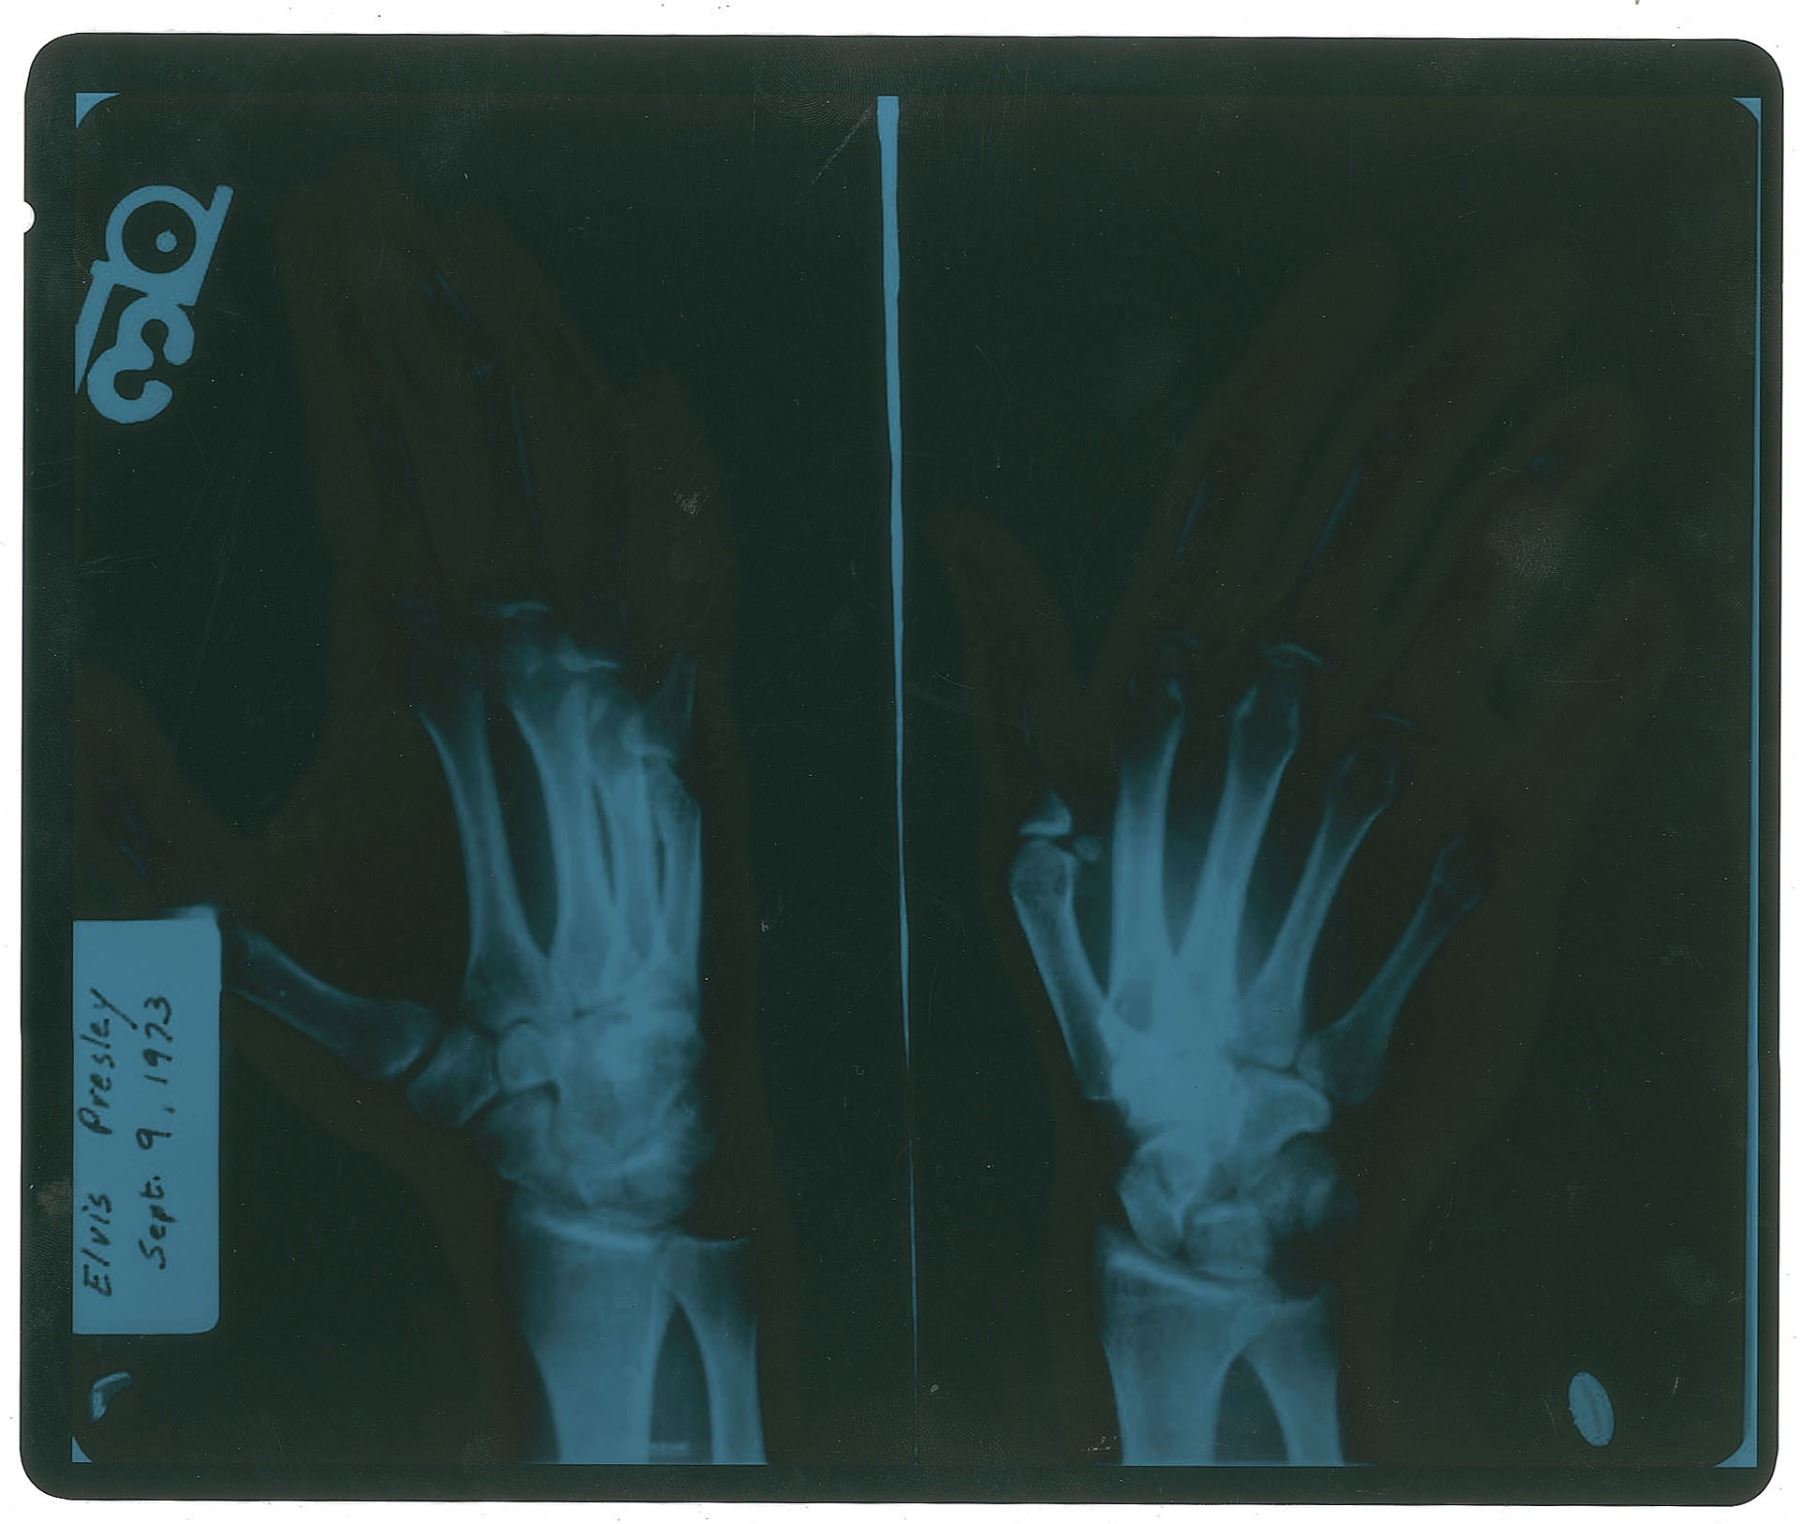

An x-ray of two images showing Elvis Presley's broken hand ordered by Dr. Elias Ghanem, 10 x 12, marked in the upper left corner, "Elvis Presley, Sept. 9, 1973." Includes three pages of copies of medical notes, including the results of a treadmill stress test, lab results, and observations from a chest exam. In fine condition. Accompanied by a copy of a letter of authenticity from Jody Ghanem and a copy of a notarized property listing from Ghanem's estate. The letter reads, in part: "These laboratory X-rays of Elvis Presley were ordered by Dr. Elias Ghanem. The X-rays are one of several that were taken of Elvis and ordered by Dr. Ghanem during the mid to late 70's to properly diagnose Elvis' injury." Elvis suffered a small fracture half way up his little finger at the fifth metacartal while performing a karate chop.